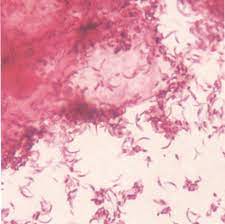

Grupa a hemolitic beta streptococ. Streptococcus pyogenes (group a streptococci). Streptococul beta hemolitic reprezintă un grup de bacterii ce cauzează infecții destul de serioase ce necesită tratament cu antibiotice.

Cele mai frecvente infecții cauzate de streptococul beta hemolitic de grup b în sarcină sunt infecțiile de tract urinar (bacteriurie asimptomatică, cistită, pielonefrită), infecții ale membranelor fetale (corioamniotită) și endometrită. Streptococcus pyogenes (group a streptococci). Beta hemolysis is a complete hemolysis of erythrocytes by the enzyme hemolysin.